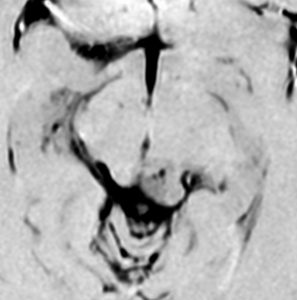

放射線化学療法後の画像です。腫瘍境界は不明瞭(左)で,腫瘍内出血(中央)して,左の視床に浸潤しています。かなりリスクは高いのですが,これを開頭手術で全摘出しました(右),この時点で完全寛解 CR です。この後にさらに化学療法と幹細胞移植(PBSCT,大量化学療法)が加えられました。